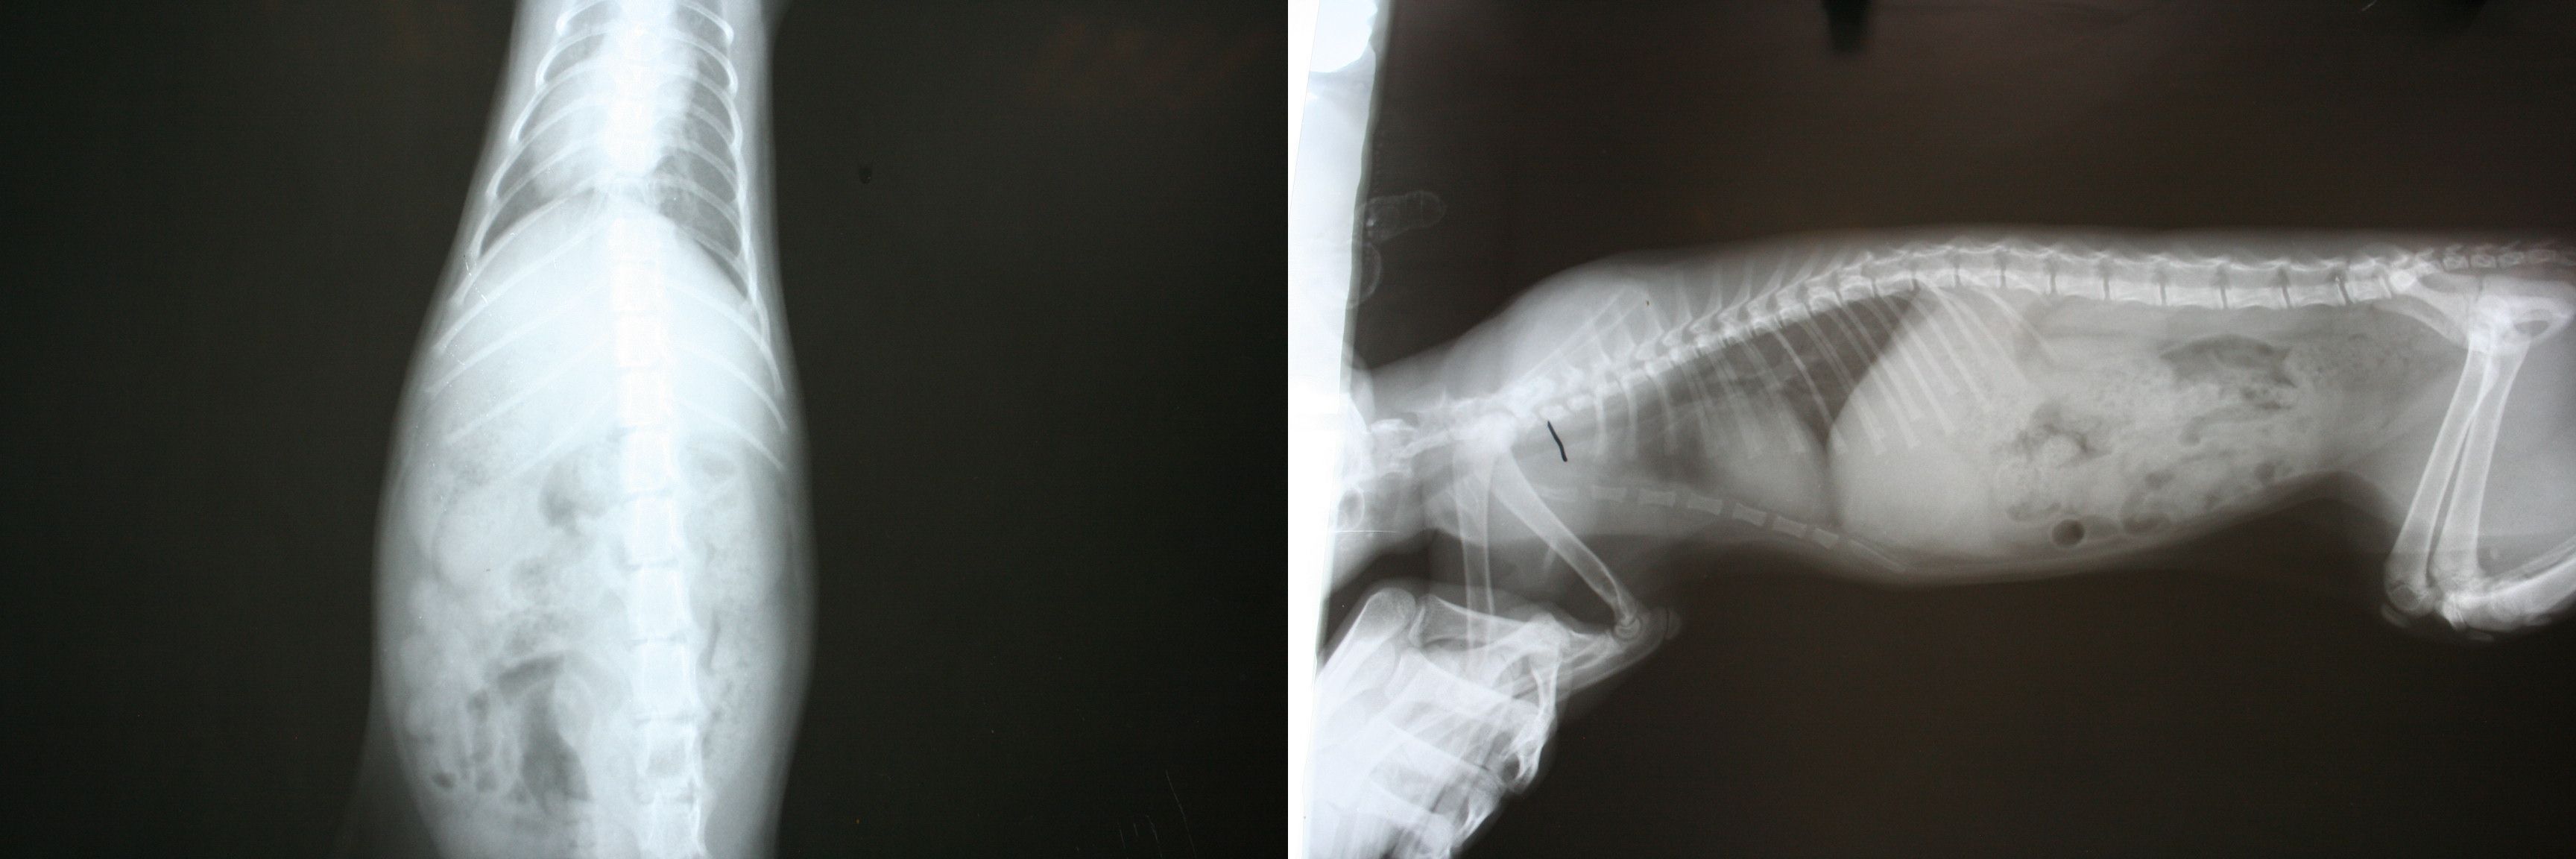

照了X光後發現肋骨有斷裂~

經過醫師醫治.鼻子流血小貓.之前肋骨斷裂處.已慢慢癒合

5.x光片檢查2張800